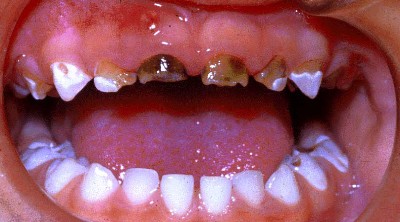

Alle fakta viser, at fluorid ikke har noget med cariesfrihed at gøre. Og cariesfrihed er det vi ønsker for risikopatienterne og alle andre. Netop for risikopatienterne er forskernes forbryderiske udtalelser gift. Når man har set små børn med masser af huller, skrigende af smerter og angst i tandlægestolen; og man ved, at fluor er medvirkende årsag, fordi det får folk til at slække på plakfjernelsen. Så undrer man sig over, at myndighederne tillader, at kvaksalvere, der burde sidde bag tremmer, går frit omkring. At kalde det videnskabelig uredelighed er århundredets underdrivelse.

Med kampagner og anbefalinger om fluor og sukker er der sat spørgsmålstegn ved tandplejens reelle hensigter. Det er kun regelmæssig plakfjernelse der kan give cariesfrihed. Alle andre metoder kan kun medføre en sænket cariesprogressionshastighed. Sålænge der er plak på tænderne vil der være caries. Uden plak er der ingen caries, helt uafhængigt af fluor og sukker. Stadig flere er cariesfrie, en cariesfrihed som helt uden tvivl er opnået ved bedre plakfjernelse. Men der er stadig risikopatienter med caries som har brug for bedre regelmæssig plakfjernelse. Den plak der er årsagen til caries på risikopatienternes tænder, har de netop på grund af den forvirring som kvaksalverne skaber omkring plakfjernelse med sukker og fluor. De har ikke skyggen af bevis for at de cariesfri bruger mindre sukker eller mere fluor. Vi burde for længst have været cariesfrie allesammen. Men sålænge kvaksalverne får lov til at udbrede deres løgne, vil der være ofre der falder for dem. Små børn vil til stadighed komme grædende til tandlægen med huller i tænderne forårsaget af plak der ikke er blevet fjernet på grund af de skadelige fluor- og sukkerkampagner.